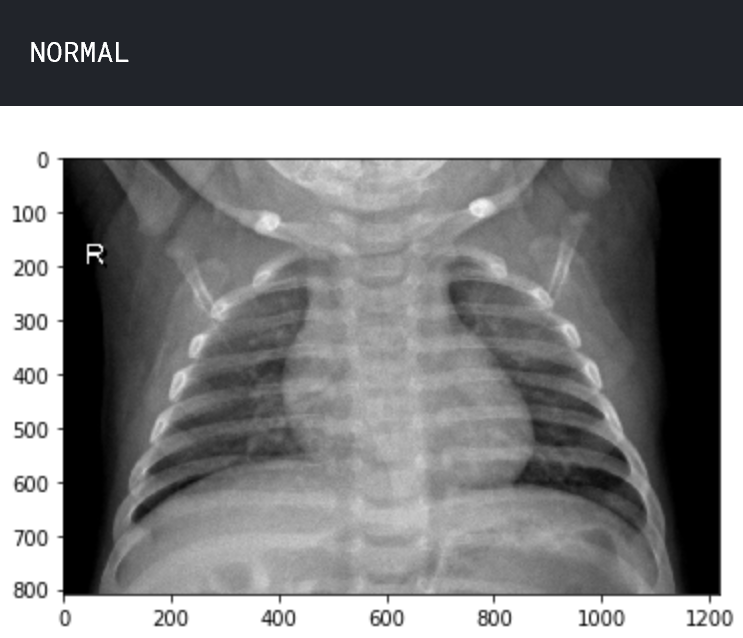

让我们了解数据。查看两个样本图像,一个处于正常状态,另一个处于肺炎状态。

plt.imshow(img_normal)

plt.show()